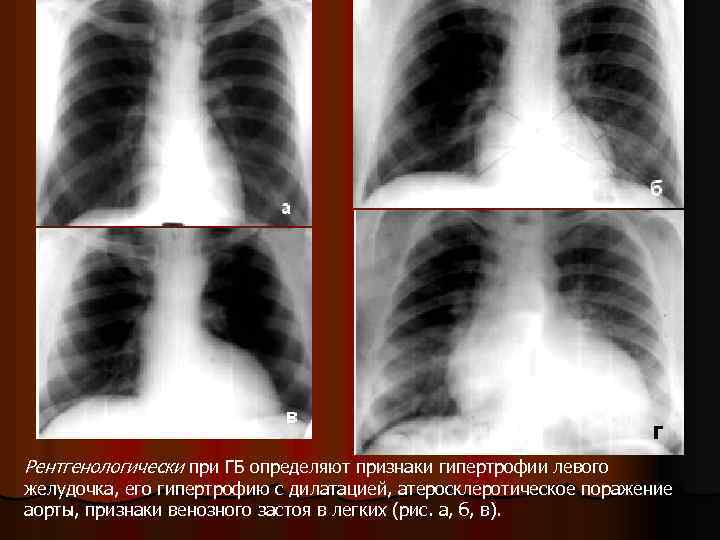

Рентгенологически при ГБ определяют признаки гипертрофии левого желудочка, его гипертрофию с дилатацией, атеросклеротическое поражение аорты, признаки венозного застоя в легких (рис. а, б, в).